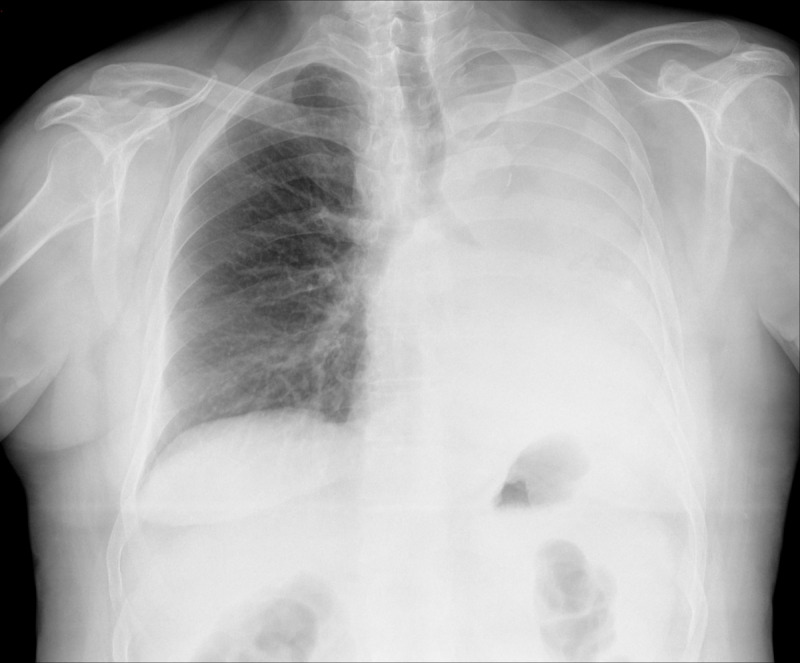

Methods: Teams of 3-4 final-year medical students, during a 2-week radiology clerkship, had access to 7 clinical cases in virtual clinical stations and were randomly assigned 2 to solve and submit. They later discussed the cases in a synchronous virtual meeting and attended an emergency radiology seminar. The experience was repeated over 2 consecutive years to assess reproducibility through comparison of learning outcomes and students' perceptions. Learning outcomes were evaluated through team-based case resolution and individual seminar assessments. Students' perceptions were gathered via a voluntary questionnaire including 5-point Likert scale items, cognitive load ratings, 10-point evaluations, and open-ended comments.

Results: In total, 182 students participated in 2020-2021 and 170 in 2021-2022, demonstrating strong team-based case resolution skills with mean scores of 7.36 (SD 1.35) and 8.41 (SD 0.99), respectively (P<.001). The perception questionnaire had a 90.6% response rate. The highest cognitive load was observed in avatar editing (median 7, 95% CI 6.56-6.96). Case-solving cognitive load was significantly lower in 2021-2022 compared with 2020-2021 (median 6, 95% CI 5.69-6.21 vs 5.10-5.66; P<.001). The students rated the experience highly, with average scores exceeding 8.0 out of 10 across various aspects. Notably, the highest-rated aspects were the teaching staff (9.13, SD 1.15), cases (8.60, SD 1.31), project organization (8.42, SD 1.67), and virtual rooms (8.36, SD 1.62). The lowest-rated aspect was internet connectivity (6.68, SD 2.53). Despite the positive scores, all aspects were rated significantly lower in 2021-2022 compared with 2020-2021. These year-to-year comparisons in performance and perception support the reproducibility of the experience.